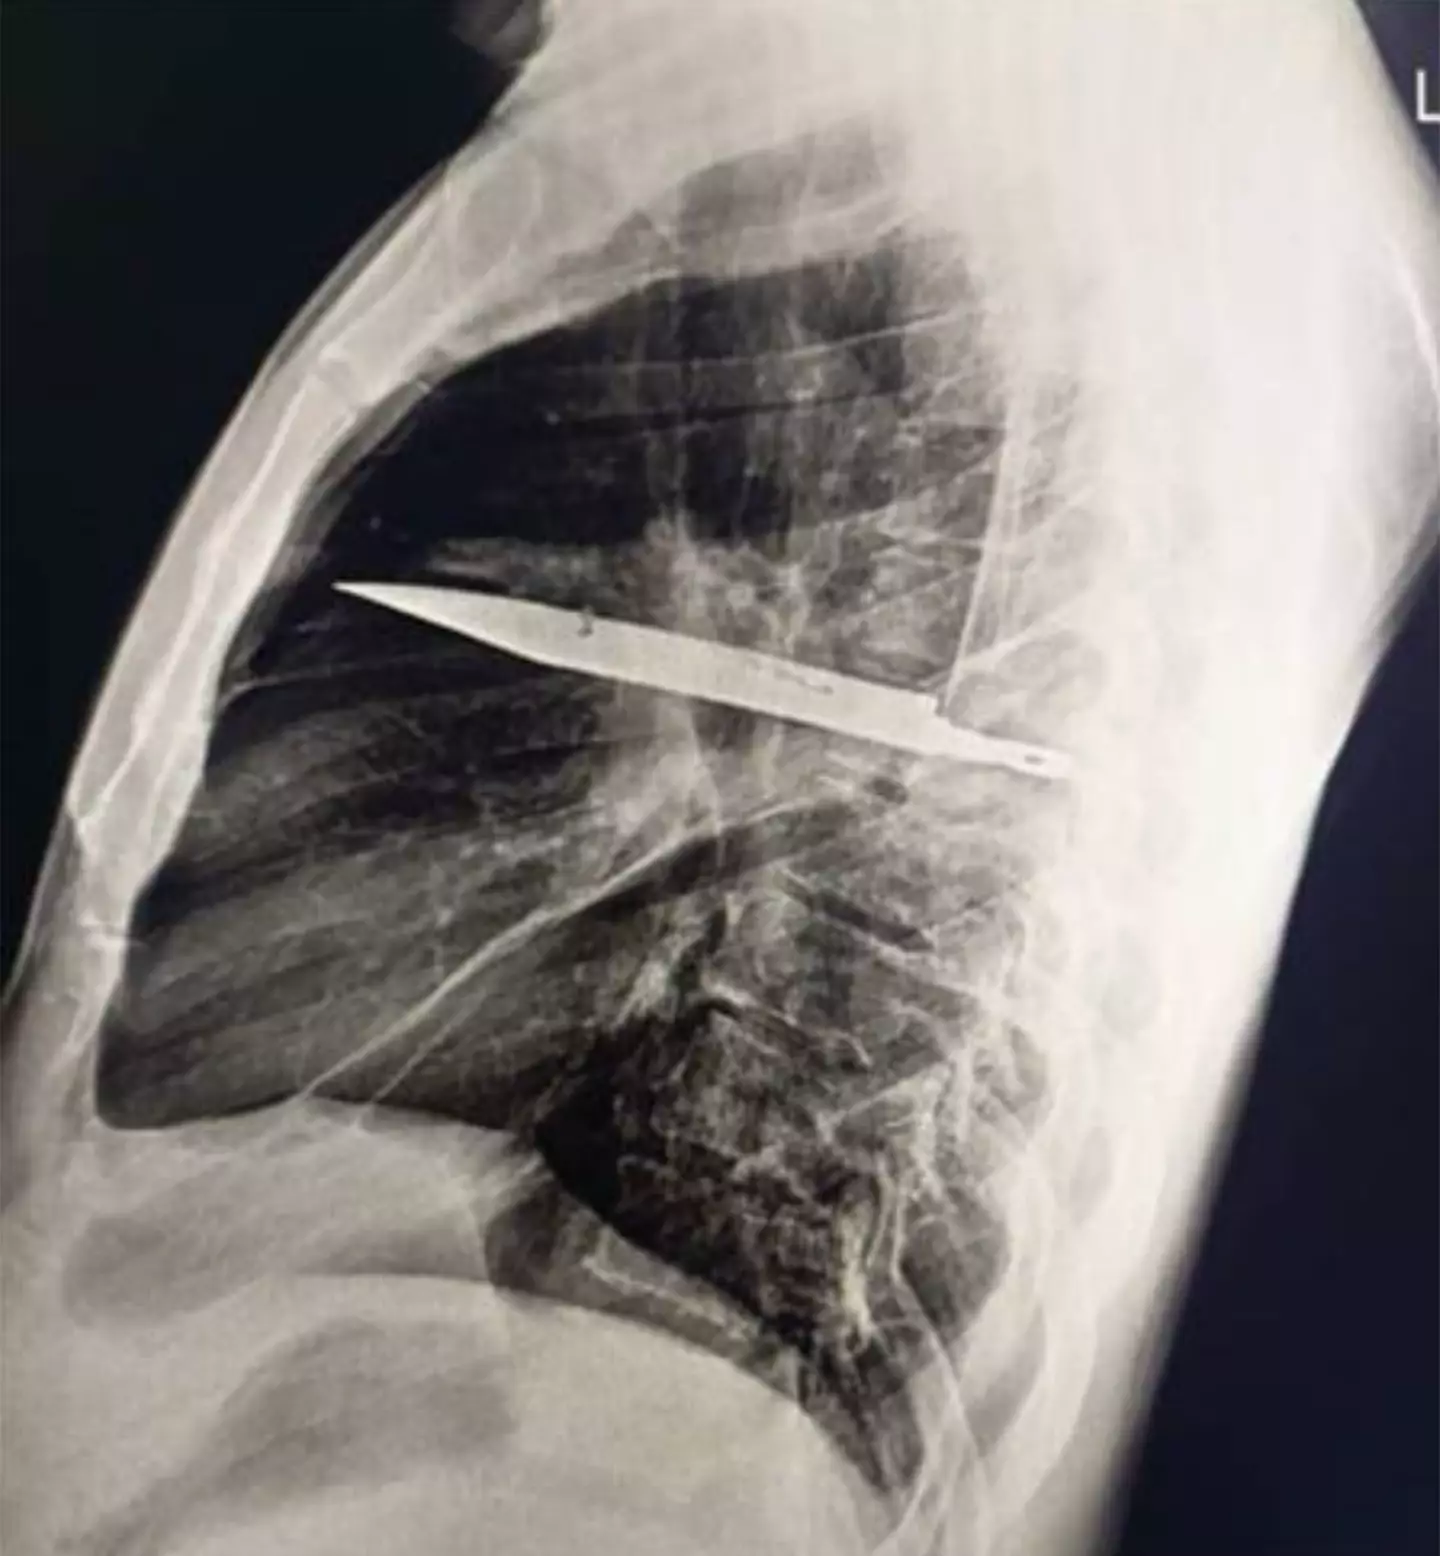

After discovering the blade, which x-rays showed had entered into the chest through the man’s right shoulder area, he was hospitalized.